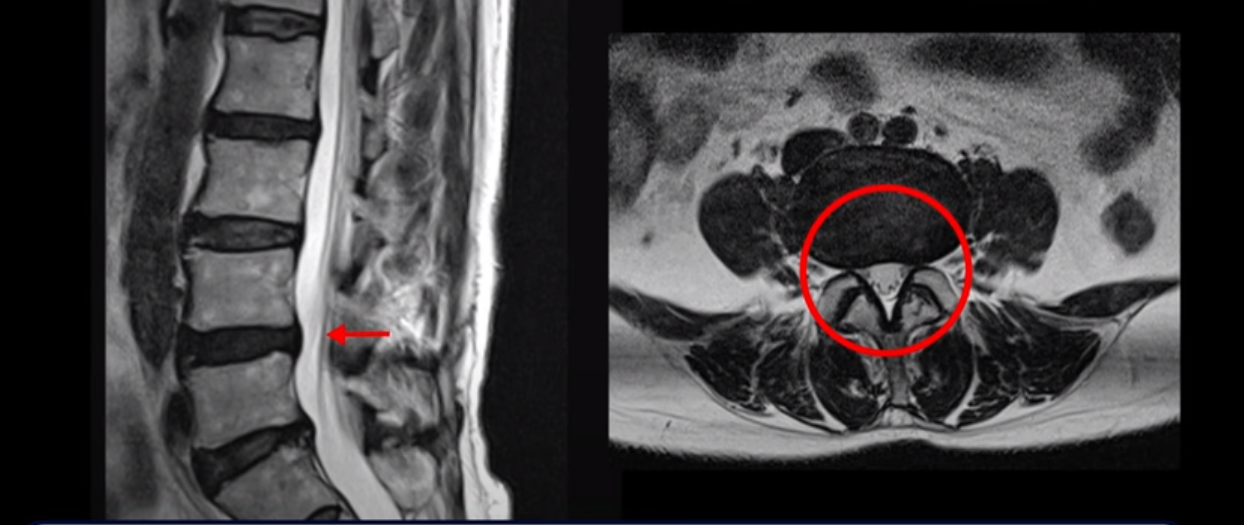

척추관이 가장 좁아진 4번 5번을 보면 중심성 협착이 있지만 많이 심하지는 않습니다